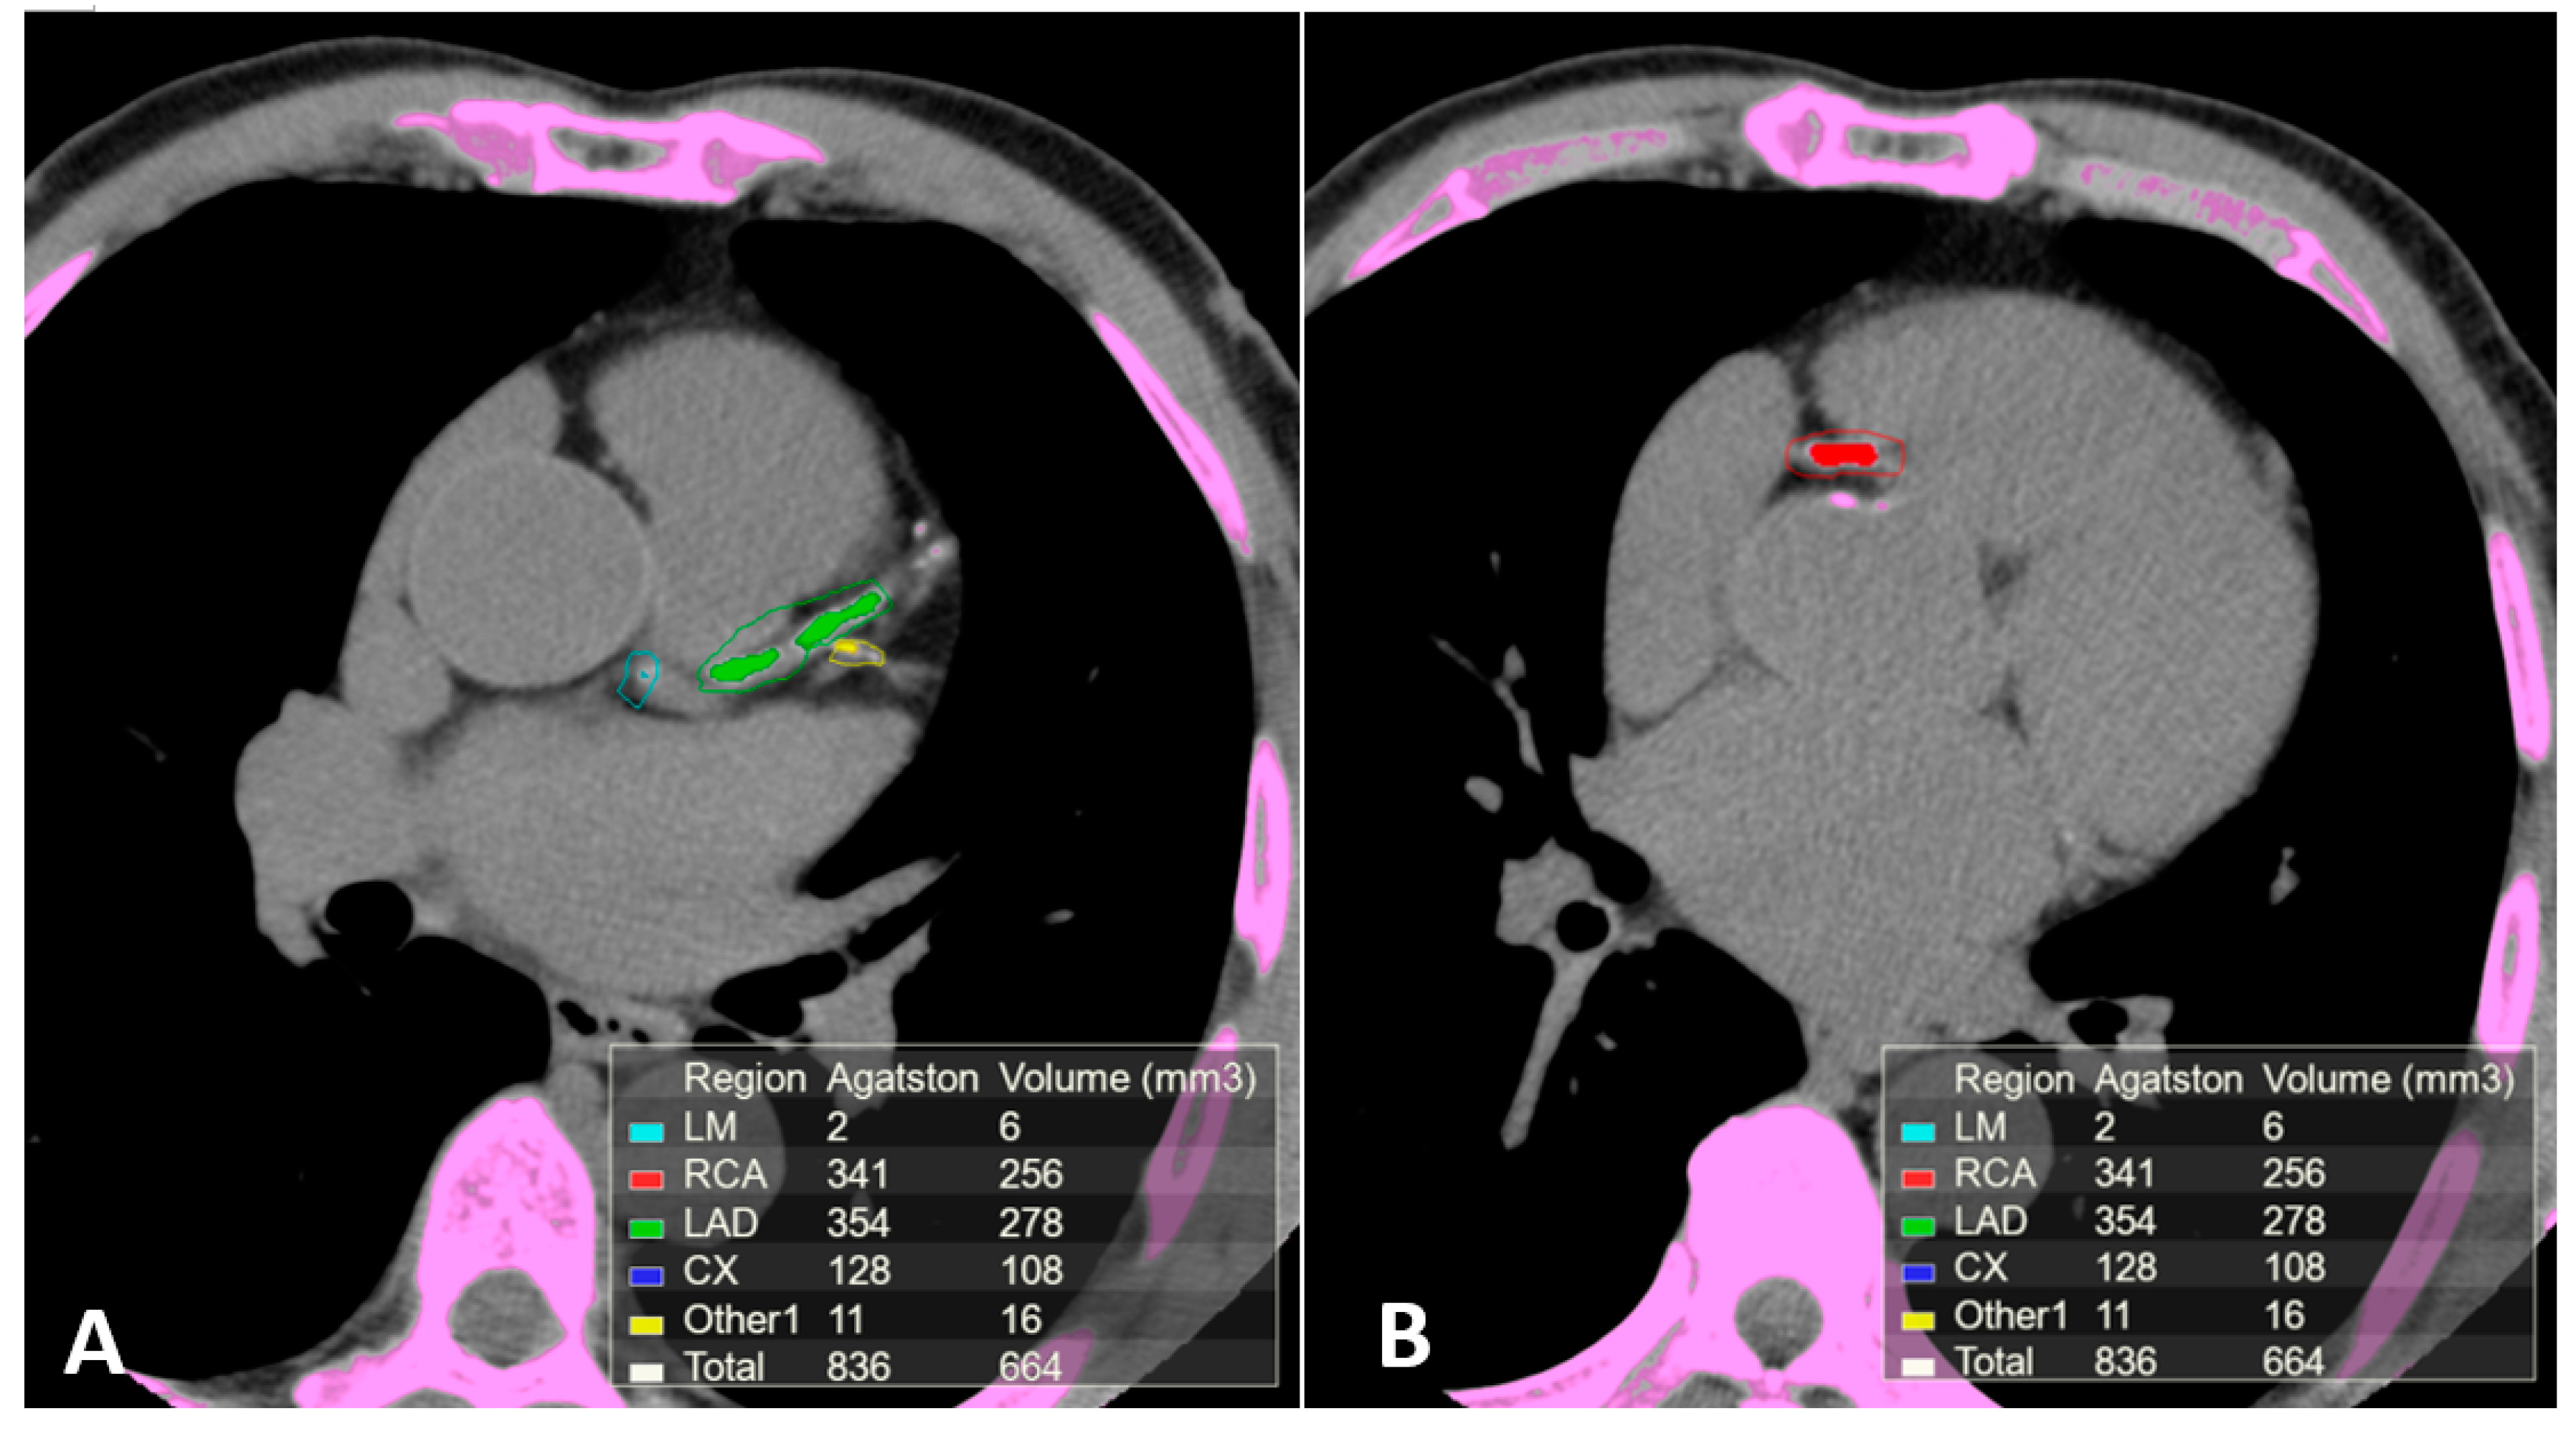

Non-contrast electrocardiographic (ECG)-gated multidetector CT provides a direct quantitative assessment of coronary artery calcium (CAC) [44]. (Figure 1). The standard method for CAC quantification is the Agatston score which measures the density of calcification in each coronary segment, multiplied by the area and summed for all arteries [45]. CAC score correlates with the total coronary plaque burden and is an independent predictor for CV events irrespective of ages [46,47,48,49,50,51,52]. Extensive calcification is associated with higher risk of CAD, because the presence of more plaques increases the chance that one may rupture. Current guidelines recommend CAC score assessment in individuals at low- to intermediate-risk in whom treatment decision may be improved by CV risk stratification [53,54,55,56]. In individuals without known atherosclerotic disease, a CAC score of zero is associated with a high negative predictive value in excluding significant CAD [57]. However, although only 5% of individuals with zero CAC have significant stenosis, low CAC scores do not exclude obstructive CAD [57,58,59]. Instead, a CAC score >100 is associated with a risk of events similar to patients with previous CAD [60,61].

Figure 1.

Calcium scoring (CAC) performed on a non-contrast ECG-gated CT scan of a patient with coronary arteries calcifications using commercial software Vitrea 6.0. The software automatically highlights all the structures attenuating at least 130 Hounsfield units (pink). Regions of interest (ROI) were manually placed around the coronary arteries calcifications using different colors for each coronary segment. The partial and overall Agatston score and volume of the calcifications included in the regions of interest are summarized in the box on the bottom of the images. (A) Calcifications in the left main, anterior descending and 1st diagonal branch. (B) Calcification in the proximal segment of the right coronary artery.